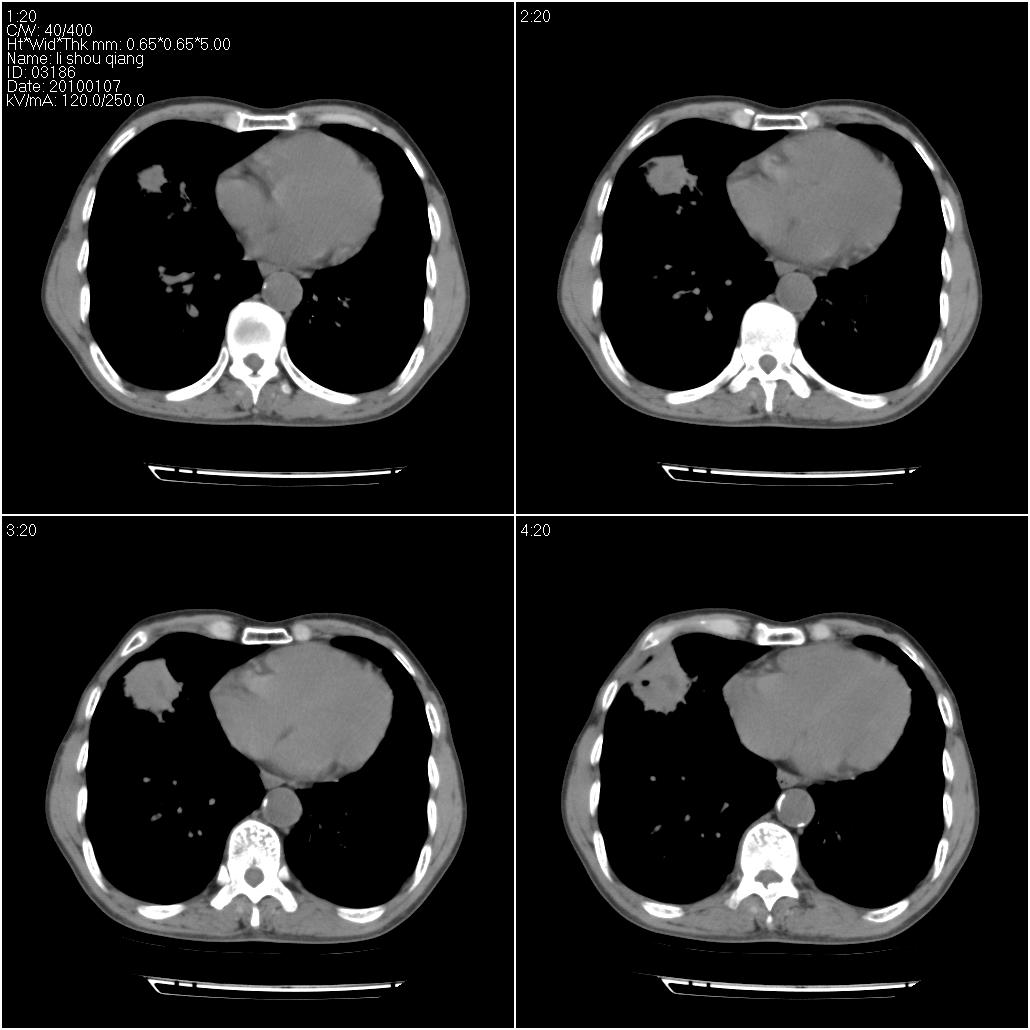

标题: CT24038:男性,58岁。主因咳嗽带血性CT检查。 [打印本页]

标题: CT24038:男性,58岁。主因咳嗽带血性CT检查。

右肺中叶外侧段见一不规则的软组织肿块,边缘可见毛刺,并见厚壁空洞,与胸膜分界欠清。另左下肺见多个小囊状扩张区

右肺中叶外侧段可见团块影,外形不规则,内见空泡征。左下肺见蜂窝状低密度透亮影,部分层面主动脉旁瘤样突出。考虑右肺中叶外围型肺癌可能性大,左下肺支气管扩张,主动脉弓瘤样突出。

考虑右肺癌可能性大,左下肺支气管扩张,主动脉弓瘤样突出?建议增强